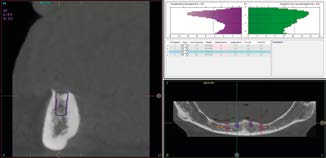

Trước khi bắt đầu quy trình cấy ghép Implant ngắn 6.5mm BTI, tất cả bệnh nhân tiêu xương dọc đều trải qua quy trình chẩn đoán toàn diện, bao gồm chụp cắt lớp vi tính chóp nón (CBCT), mẫu hàm nghiên cứu và sáp chẩn đoán (diagnostic wax-ups). Phân tích 3D của phần xương còn lại giúp xác định vị trí, góc độ và đường kính Implant một cách chính xác.

Các Implant ngắn 6.5mm BTI được đặt bằng cách sử dụng quy trình khoan định hướng sinh học (biologically guided drilling protocol) độc quyền của BTI, với lực vặn chèn được đo tại thời điểm đặt để xác nhận sự phù hợp cho việc chịu lực tức thì. Các phục hình tạm thời liên kết bắt vít được gắn ngay sau phẫu thuật để ổn định sự phân bố lực trong quá trình tích hợp xương. Từ 3 đến 6 tháng sau, chúng sẽ được thay thế bằng các cầu răng sứ kim loại cố định hoặc phục hình lai kim loại-nhựa, đảm bảo phục hình hoàn hảo cho bệnh nhân tiêu xương dọc.

3.2. Lên kế hoạch mô phỏng và ứng dụng Implant ngắn 6.5mm BTI